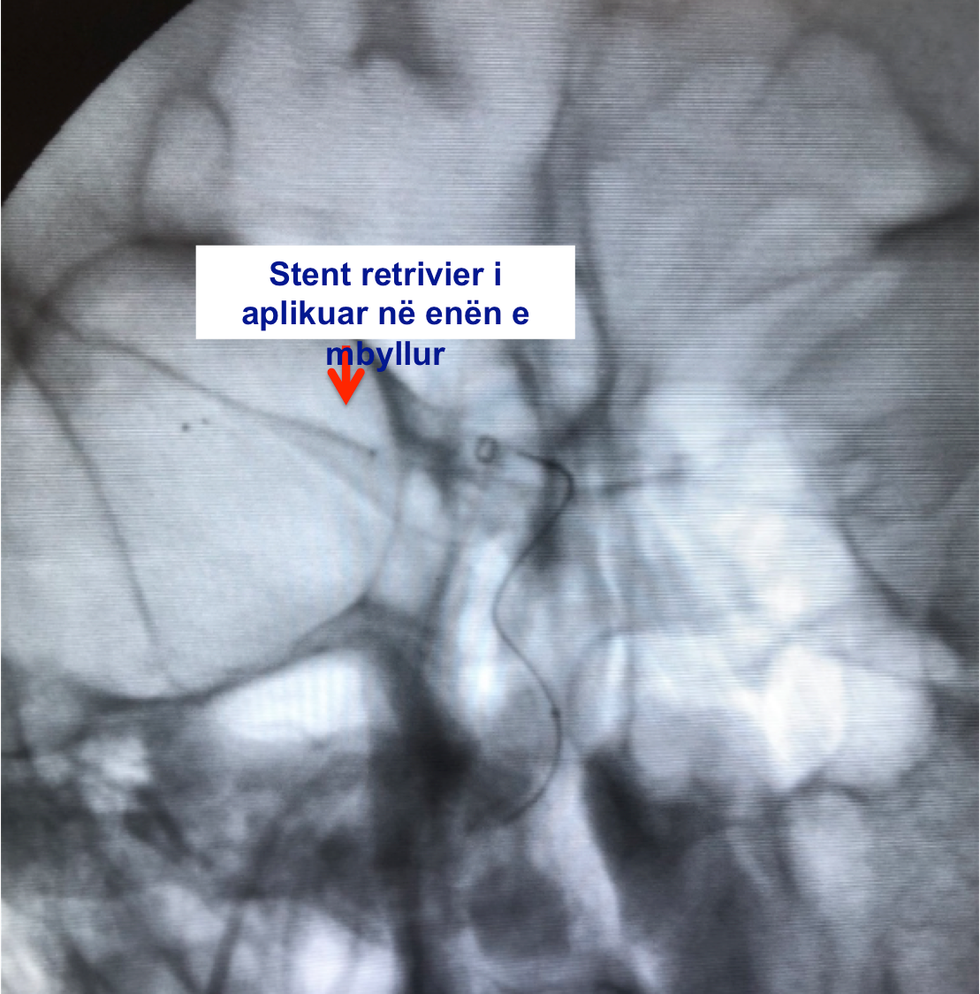

Ekipi i radiologëve për herë të parë ka përdorur stentin (retriever) për heqjen e gjakut të ngjizur (trombit )në arteriet e trurit (kokës) dhe rihapjes së qarkullimit të gjakut në tru.

Stent retriever është një produkt shumë i avancuar i cili ndihmon në kapjen dhe tërheqjen e trombit (gjakut të ngjizur) dhe rihapjes së enës së gjakut. Me rivendosjen e qarkullimit të gjakut në enën e mbyllur, mundësohet të furnizohet me ushqim dhe oksigjen pjesa e trurit e cila është e rrezikuar të dëmtohet, me çka i rikthehen funksionet të cilat filluan të humben (varësisht nga regjioni i dëmtuar i trurit).